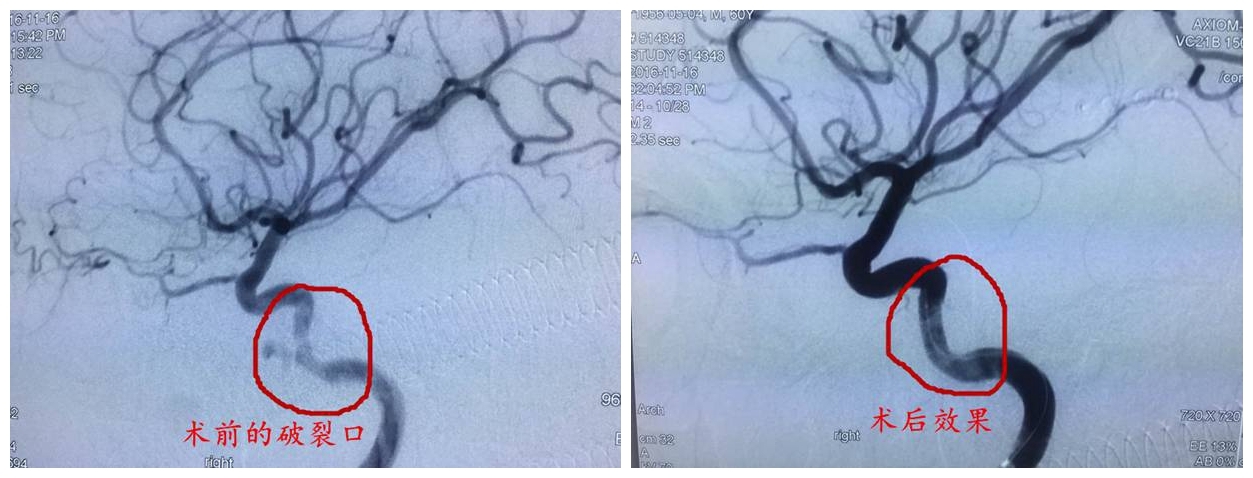

神经外科李雪松主任对该病例高度重视,邀请了介入科、DSA导管室、肿瘤科、耳鼻喉科、麻醉科、ICU进行多学科联合诊疗,为患者制定最优化的治疗方案。11月16日,李雪松主任在饶强医生的配合下,对患者施行了全脑血管造影术,术中造影果然发现了右侧颈内动脉海绵窦段假性动脉瘤。经与家属共同决策,李主任采取了覆膜支架介入手术,术程顺利,术后患者恢复良好。

此次手术运用新型覆膜支架植入技术,具有血管内膜覆盖撕裂片的作用,能有效地防止血管内膜破裂、动脉形成等并发症。作为一项新的治疗技术,手术难度大、风险高,术中操作精度要求高,全国仅有少数大型医院能够实施,这也是我院开展的首例该项技术。